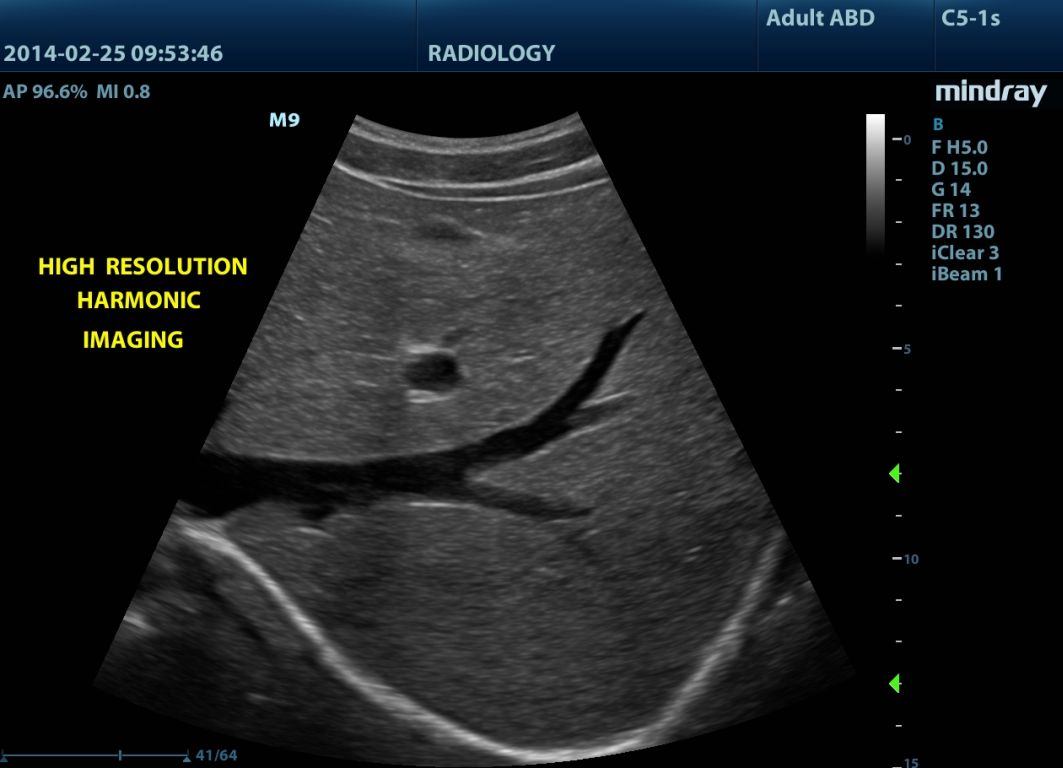

Mindray M9 je dopplerovský ultra ľahký prenosný UZV prístroj najvyššej High End triedy s použitím single crystal 3T sond (vynikajúce zobrazenie blízkeho i vzdialeného poľa), HDR FLOW, ECHO BOOST, Natural Touch Elastography, kontrastného zobrazenia, TDI. Špeciál hlavne pre kardiológiu.

Klinické obrázky:

- iBeam

- iClear (digitálne filtre na odstránenie ultrazvukového šumu a zvýraznenie rozhraní)